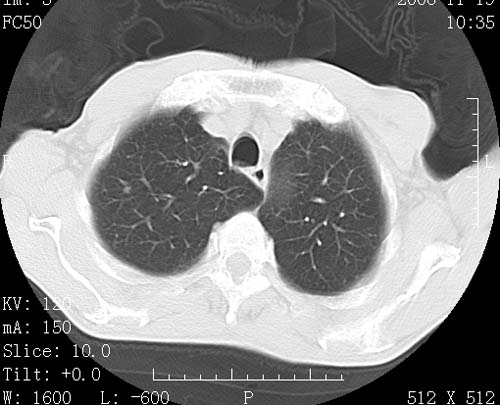

术前查体,双肺部结节是转移?结核?请点评

1)符合食管癌表现。2)两肺及纵隔淋巴结多发性转移瘤。3)左肺上叶舌段及两肺下叶炎症感染。

食管癌伴双肺转移,评述:肺部毛细血管网丰富,全身血液均快速流经肺部,癌细胞容易过滤定植,形成转移瘤,影象特点为以毛细血管末梢为中心的结节灶,边缘光滑锐利,少见有中心空洞着,不同来源的转移瘤可有各自特点,如甲状腺癌为双肺弥漫性微结节,本例有原发灶,双肺影象灶典型,左肺舌段条带状网格样伴胸膜天幕征,可视为癌性淋巴管炎。